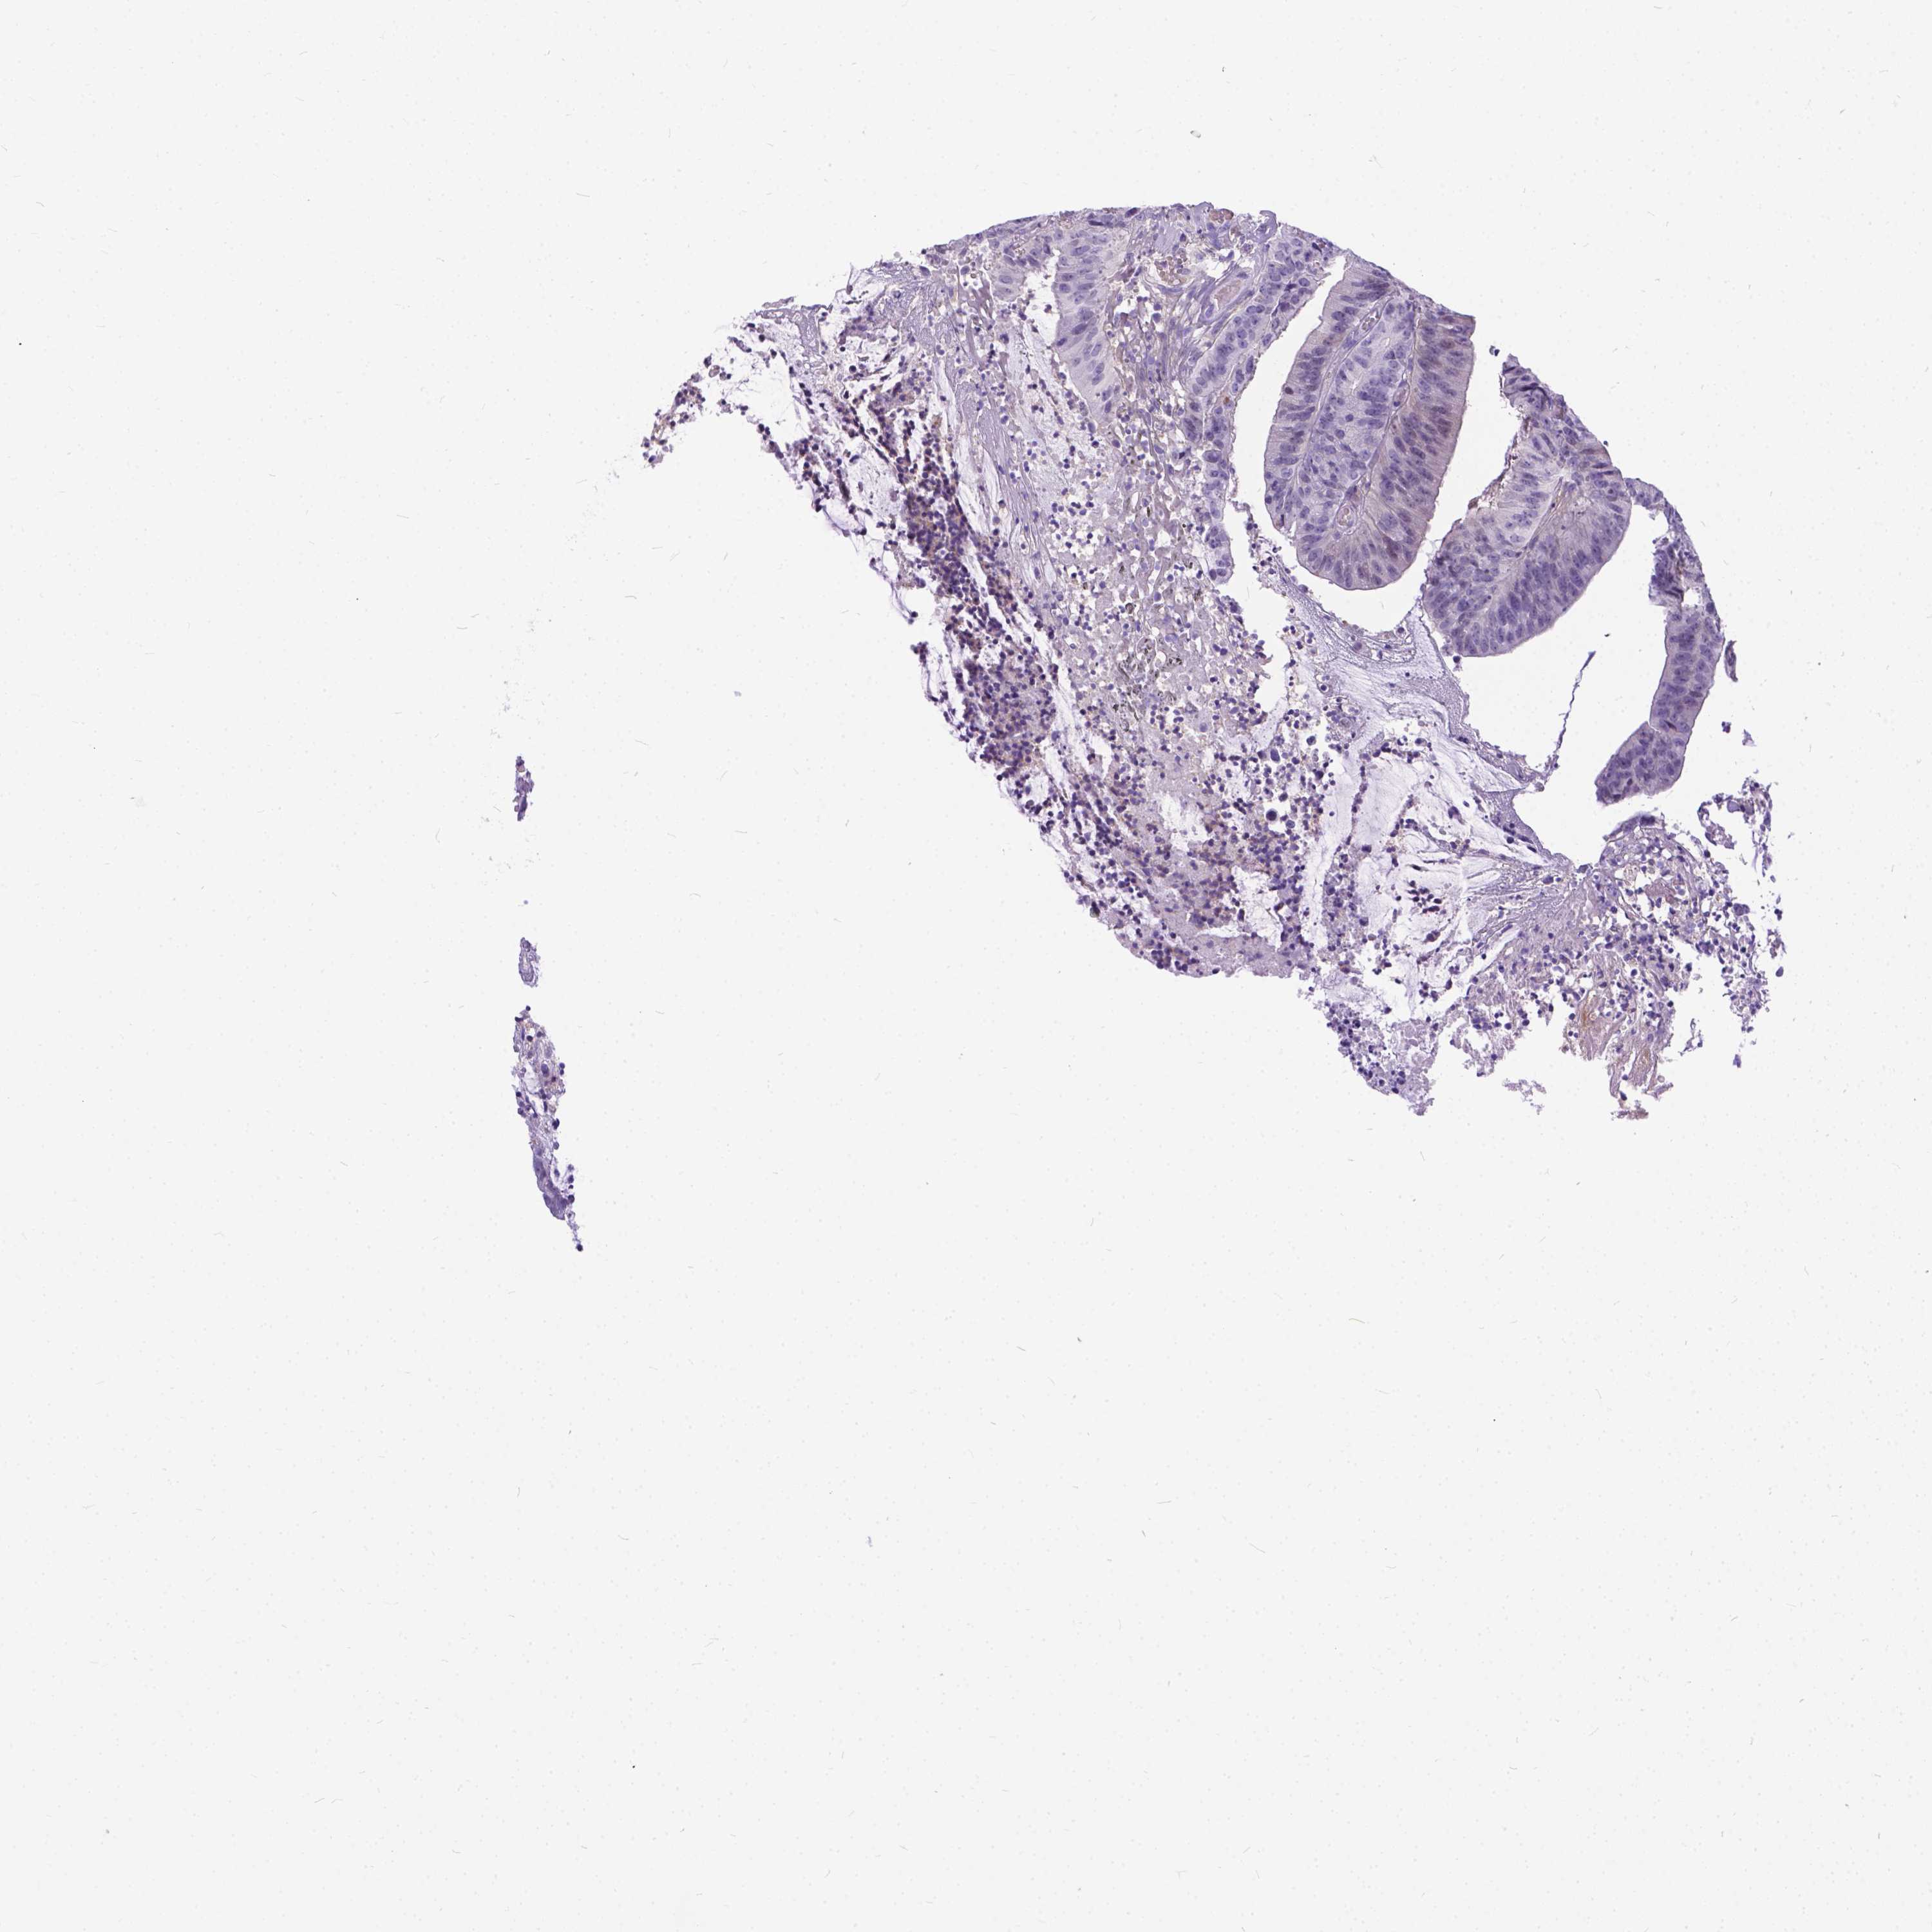

CANCER COLORECTAL CANCER Show tissue menu

Colorectal cancer

Colon adenocarcinoma